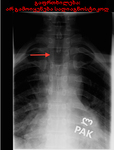

"winking owl" (ბუ, რომელიც თვალს გვიკრავს) ნიშანი (ისარი): ხერხემლის ასიმეტრია რენტგენზე, რაც გამოწვეულია მალის რკალის ფეხის დესტრუქციით

შექმნილია BMJ Publishing Group მიერ